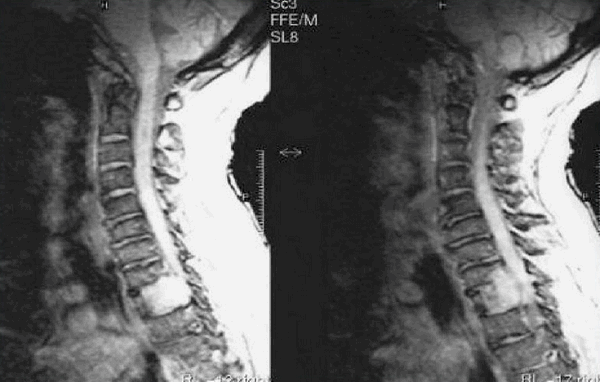

Снимки МРТ мягких тканей шеи

Проведение магнитнорезонансной томографии с использованием различных режимов повышает информативность исследования рыхлых элементов. Изучение особенностей кровоснабжения зоны интереса и диагностика новообразований требуют применения контрастного раствора. В качестве «окрашивающего» препарата используют хелаты гадолиния.

Мягкие ткани шеи на МРТ

Магнитно-резонансное сканирование может применяться в качестве основного или дополнительного метода исследования в диагностике эндокринных заболеваний.